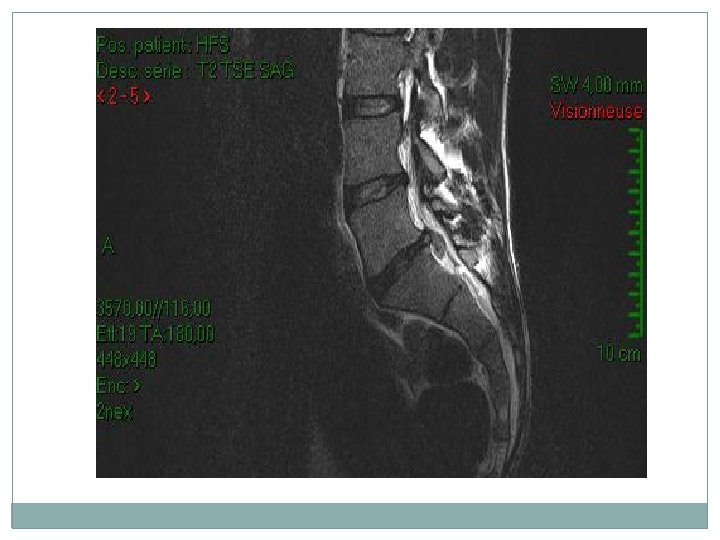

L’imagerie par résonance magnétique (IRM) lombosacrée �L'analyse des migrations herniaires et des sténoses canalaires associées. • L'exploration d'emblée de 1'ensemble des disques lombaires grâce aux coupes sagittales. • L'exploration du compartiment intradural.